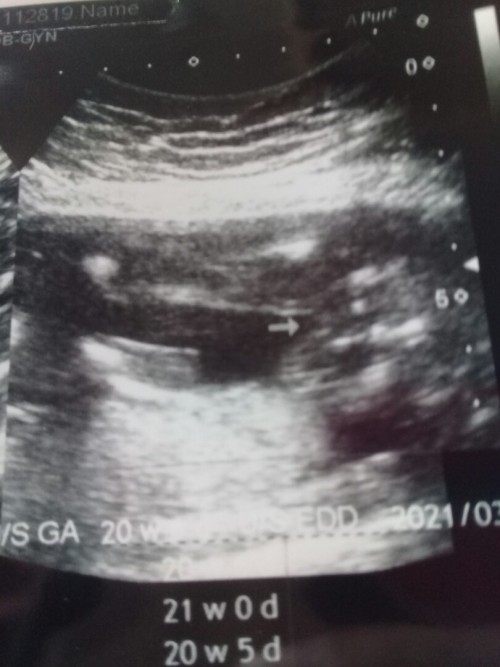

บ้านนี้20วีคคะ เเต่น้องหนีบขา